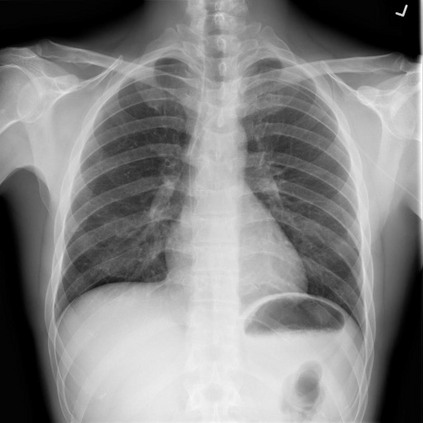

The latest breakthroughs in large vision-language models, such as Bard and GPT-4, have showcased extraordinary abilities in performing a wide range of tasks. Such models are trained on massive datasets comprising billions of public image-text pairs with diverse tasks. However, their performance on task-specific domains, such as radiology, is still under-investigated and potentially limited due to a lack of sophistication in understanding biomedical images. On the other hand, conversational medical models have exhibited remarkable success but have mainly focused on text-based analysis. In this paper, we introduce XrayGPT, a novel conversational medical vision-language model that can analyze and answer open-ended questions about chest radiographs. Specifically, we align both medical visual encoder (MedClip) with a fine-tuned large language model (Vicuna), using a simple linear transformation. This alignment enables our model to possess exceptional visual conversation abilities, grounded in a deep understanding of radiographs and medical domain knowledge. To enhance the performance of LLMs in the medical context, we generate ~217k interactive and high-quality summaries from free-text radiology reports. These summaries serve to enhance the performance of LLMs through the fine-tuning process. Our approach opens up new avenues the research for advancing the automated analysis of chest radiographs. Our open-source demos, models, and instruction sets are available at: https://github.com/mbzuai-oryx/XrayGPT.